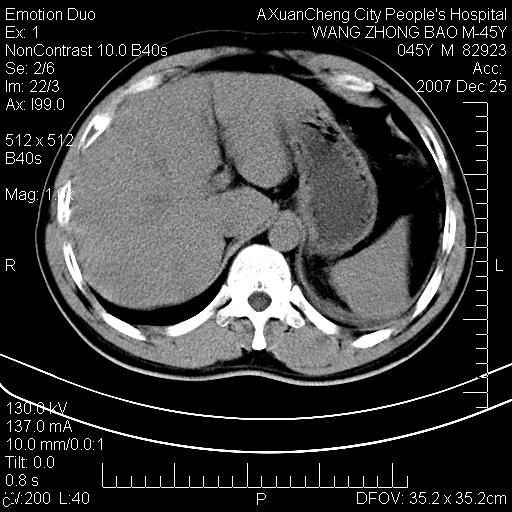

以下是引用卜一在2007-12-25 14:07:00的发言:[br]胰头钩部略增大,与十二指肠壶腹部关系密切,其内明显见软组织密度肿块,明显强化,但肠壁较光滑 柔软。考虑:炎性增生!建议消炎后复查!待除外壶腹部腺癌!

以下是引用zjzjr在2007-12-25 13:35:00的发言:[br]考虑正常的十二指肠乳头部,建议胃镜检查.

以下是引用qiuleiyu在2007-12-25 18:14:00的发言:[br]胰腺增大,周边渗出改变,肾前筋膜明显增厚,示少量积液.胆囊壁毛糙,周边少许渗出,胆总管壁厚,异常强化,然扩张不明显.结合病程急短;考虑;胆管炎,胆囊炎,胆源性胰腺炎可能大,请结合实验室检查及随访.

以下是引用lisihao在2007-12-25 14:23:00的发言:[br]急性水肿型胰腺炎[br]依据:1、胰腺弥漫性肿大,边缘稍毛糙;[br] 2、双侧肾周筋膜增厚,尤以左侧为甚(重要征象)[br] 3、双侧后胸膜增厚(刺激性炎症);[br] 4、结合病史,查血尿淀粉酶应该可以确诊。